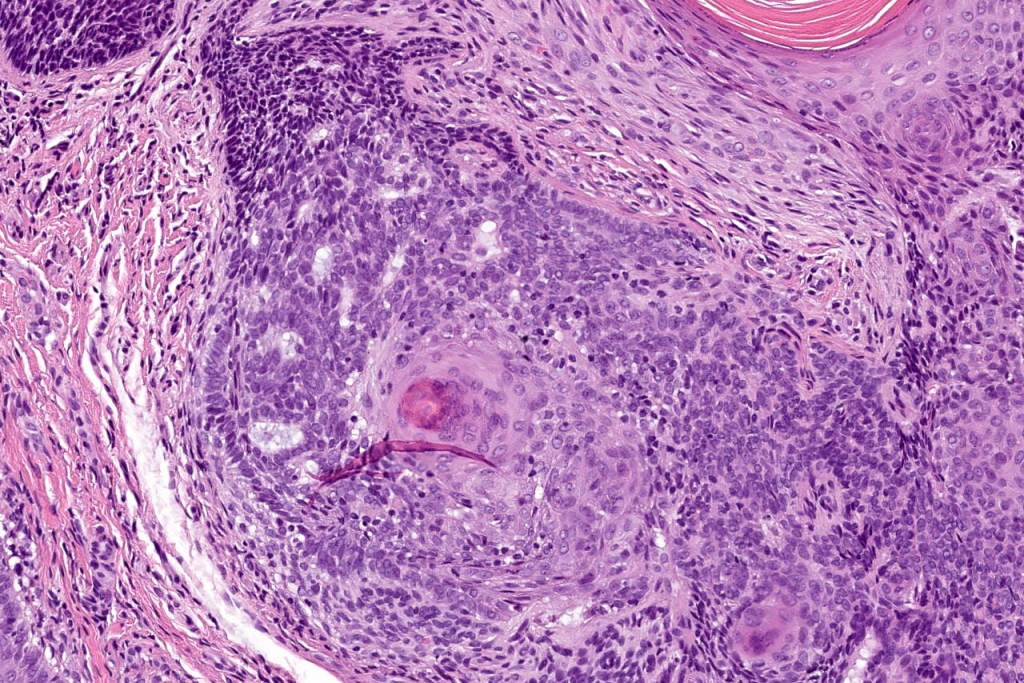

•The classical appearance consists of keratocysts & lobules of basaloid cells

•Basaloid lobules show peripheral palisading

•Perifollicular mesenchyme is always conspicuous and sometimes densely aggregated are seen indenting the baslaloid lobules (papillary mesenchymal bodies)

•Narrow epithelial strands arising from the basaloid lobules are often present

•Amyloid, foreign body granuloma formation to free keratin & calcification are variable features

Trichoepithelioma should be distinguished from trichoblastoma since the latter is very rarely syndromic. Trichoepithelioma is largely a dermal tumor whereas trichoblastoma often extends from the dermis into subcutaneous fat or deeper in very large examples. Papillary mesenchymal bodies are much better formed and generally more obvious in trichoepithelioma. Trichoepithelioma must also be distinguished from basal cell carcinoma. Retraction artifact & stromal mucin are features of basal cell carcinoma and not trichoepithelioma. Papillary mesenchymal bodies are not seen in basal cell carcinoma.